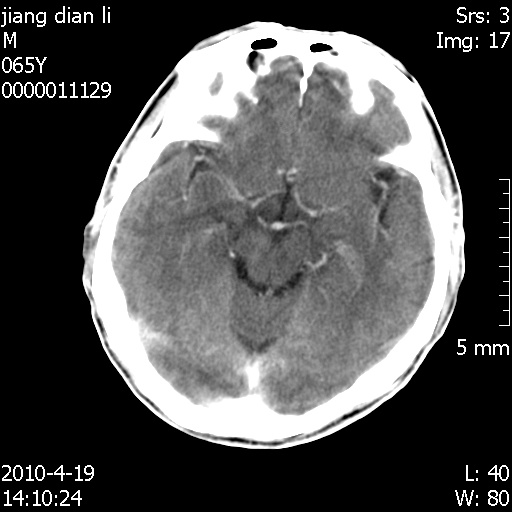

老年男性,突发左下肢无力1天,其余有价值的检查都没有。平扫ct值大约60hu,增强后ct值没什么改变,请大家讨论一下这个病例是什么?说明诊断理由。

左小脑、右大脑顶叶多发圆形高密度病灶,其周环状低密度影。考虑多发脑出血。隔期观察。

今天上班后发现病人前天复查(4月18日发病,19日初诊,22日复查),三个病灶均明显增大,边缘仍旧清楚,水肿加重,右侧脑室基本闭塞。